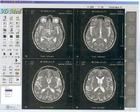

磁共振

核磁共振成像(NMRI,Nuclearmagneticresonanceimaging)磁共振成像(MRI,Magneticresonanceimaging)